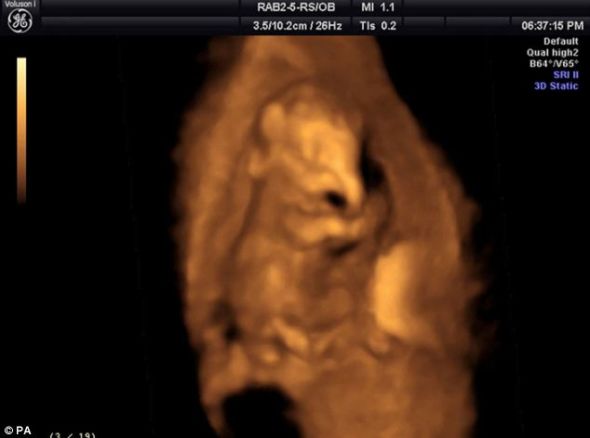

小象胎儿子宫超声波扫描图:3个月鼻子清晰可见

北京时间11月17日消息,这是一张令人难以置信的照片,它显示的是母象子宫里的一头小象胎儿,此时小家伙的象鼻已经清晰可见。

英国贝德福德郡惠普斯奈德动物园(Whipsnade Zoo)最近刚出生的小象乔治的这张照片,是在它出生的19个月前拍摄的。工作人员利用三维超声波扫描和微型照相机拍摄大象从受精到出生的整个怀孕过程。从这些妊娠大约3个月到22个月的照片里,小象胎儿清晰可见。

乔治是贝德福德郡惠普斯奈德动物园亚洲象群里一个爱闹的小家伙,它喜欢与姐姐堂娜一起在占地7英亩的围场里玩耍。动物园发言人丽贝卡·史密斯说:“我们有一个来自柏林的科研组,他们专门负责给怀孕的大象进行超声波扫描。这是一个常规程序,不过图片的清晰度有很大不同。但这是我们至今看到的最清晰的一张,微小的象鼻显然清晰可见。一看就知道它是头大象。”